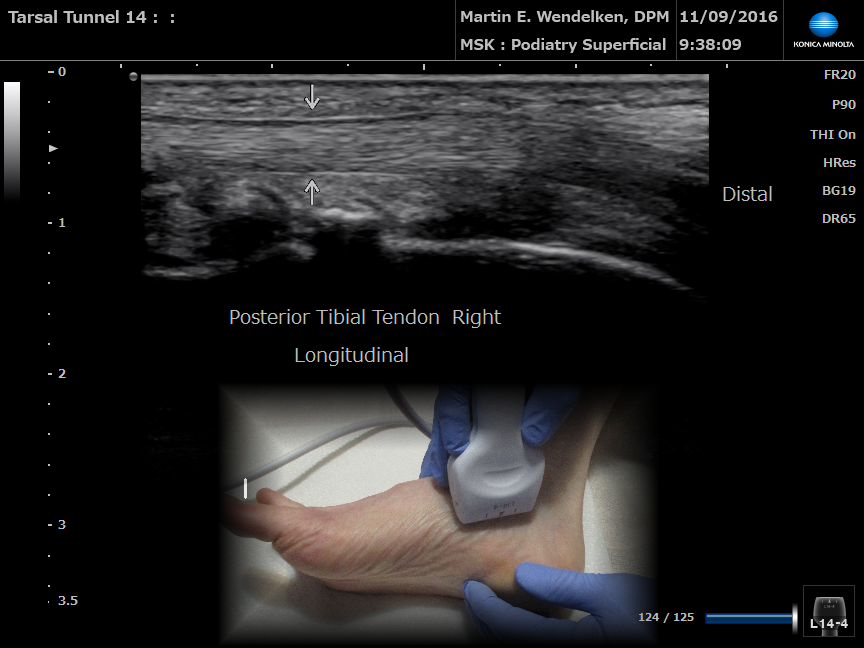

Then (2007) & Now (2020)

8MHz vs 18MHz

• Image 6: Posterior Tibial Tendon Longitudinal